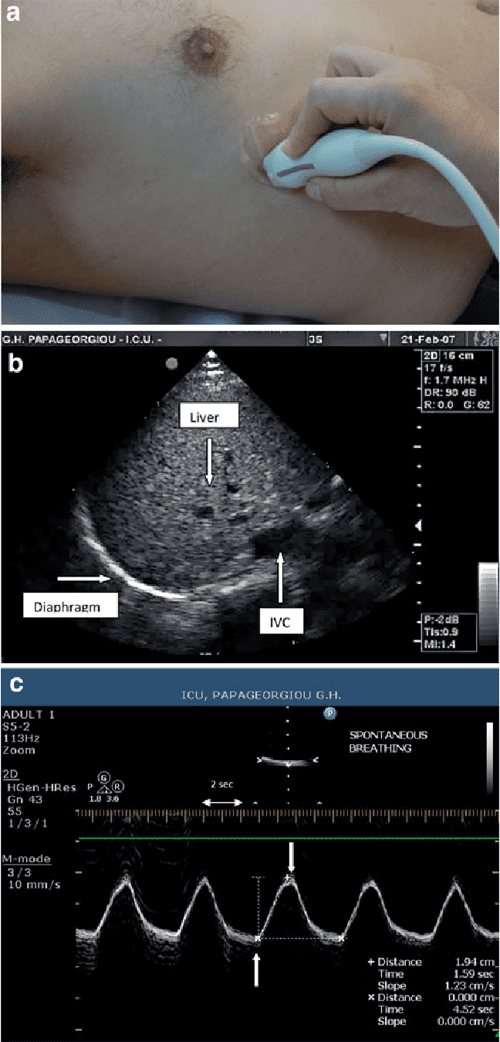

MMode Ultrasound Assessment Of Diaphragm Movement RK.MD Diaphragm Ultrasound Technique The main goals of diaphragm ultrasound in critically ill patients are: Recently, a new technique for finding the zoa was described, known as the abcde technique, which allows the diaphragm to be identified in less than 2 minutes; Diaphragmatic ultrasound has gained importance because of its many advantages,. Assessment of diaphragm function over time:. Diaphragm ultrasonography enables the diagnosis of. Diaphragm Ultrasound Technique.

Ultrasonographic measurement of diaphragm movements. C Openi Diaphragm Ultrasound Technique Diaphragm ultrasonography enables the diagnosis of conditions such as phrenic nerve palsy and diaphragm dysfunction, assessing. Diaphragmatic ultrasound has gained importance because of its many advantages,. Recently, a new technique for finding the zoa was described, known as the abcde technique, which allows the diaphragm to be identified in less than 2 minutes; Assessment of diaphragm function over time:. The. Diaphragm Ultrasound Technique.